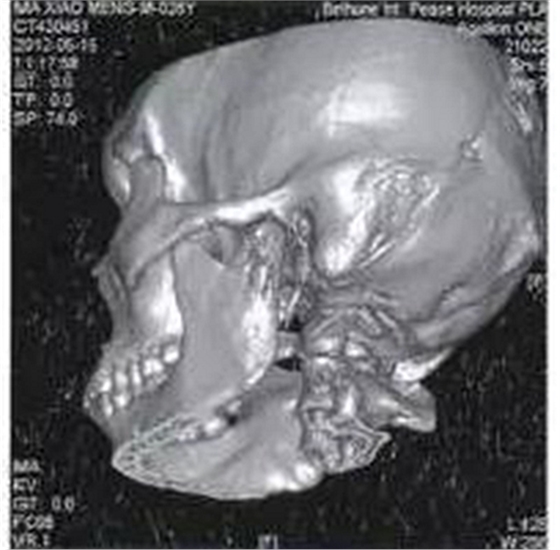

病例1,男,26歲。1月前在當(dāng)?shù)劓?zhèn)醫(yī)院拔除左上頜第三磨牙,術(shù)后3天出現(xiàn)左側(cè)面部腫脹,疼痛,張口受限,張口度約20mm,在當(dāng)?shù)剡M(jìn)行全身抗生素治療,局部未予任何處理,效果不佳。CT示左側(cè)咬肌間隙及顳下間隙腫脹,左側(cè)髁突頸部骨質(zhì)破壞,明顯死骨形成(圖1)。

圖1左側(cè)髁突骨髓炎,死骨形成

收入院后全麻下經(jīng)耳前顳部手術(shù)入路暴露病變區(qū)域,術(shù)中見左側(cè)髁突頸部外側(cè)骨皮質(zhì)破損,死骨分離。術(shù)中刮除死骨,貫通各個(gè)膿腔,引流膿液,放置引流條,抗感染治療,術(shù)后1月張口度恢復(fù)正常。